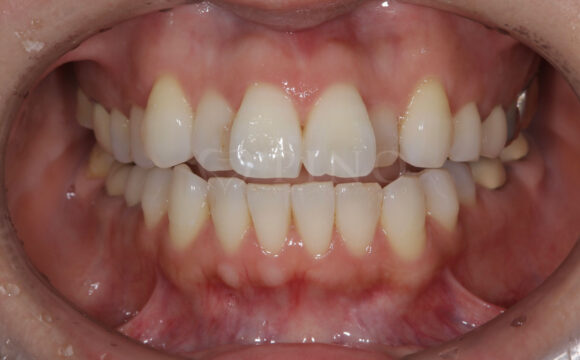

症例3:ワイヤー矯正後の後戻りが気になる(40代女性)

主訴 ワイヤー矯正後の後戻りが気になる 診断名 叢生 治療方法 マウスピース部分矯正 抜歯 なし オルソパルス なし 治療期間 9ヶ月 費用 436,000円 副作用・注意点 矯正後の後戻りを防ぐためリテーナーの使用が必要となる 備考 奥歯に噛み合わせ不良がない場合、部分矯正が適応となる -